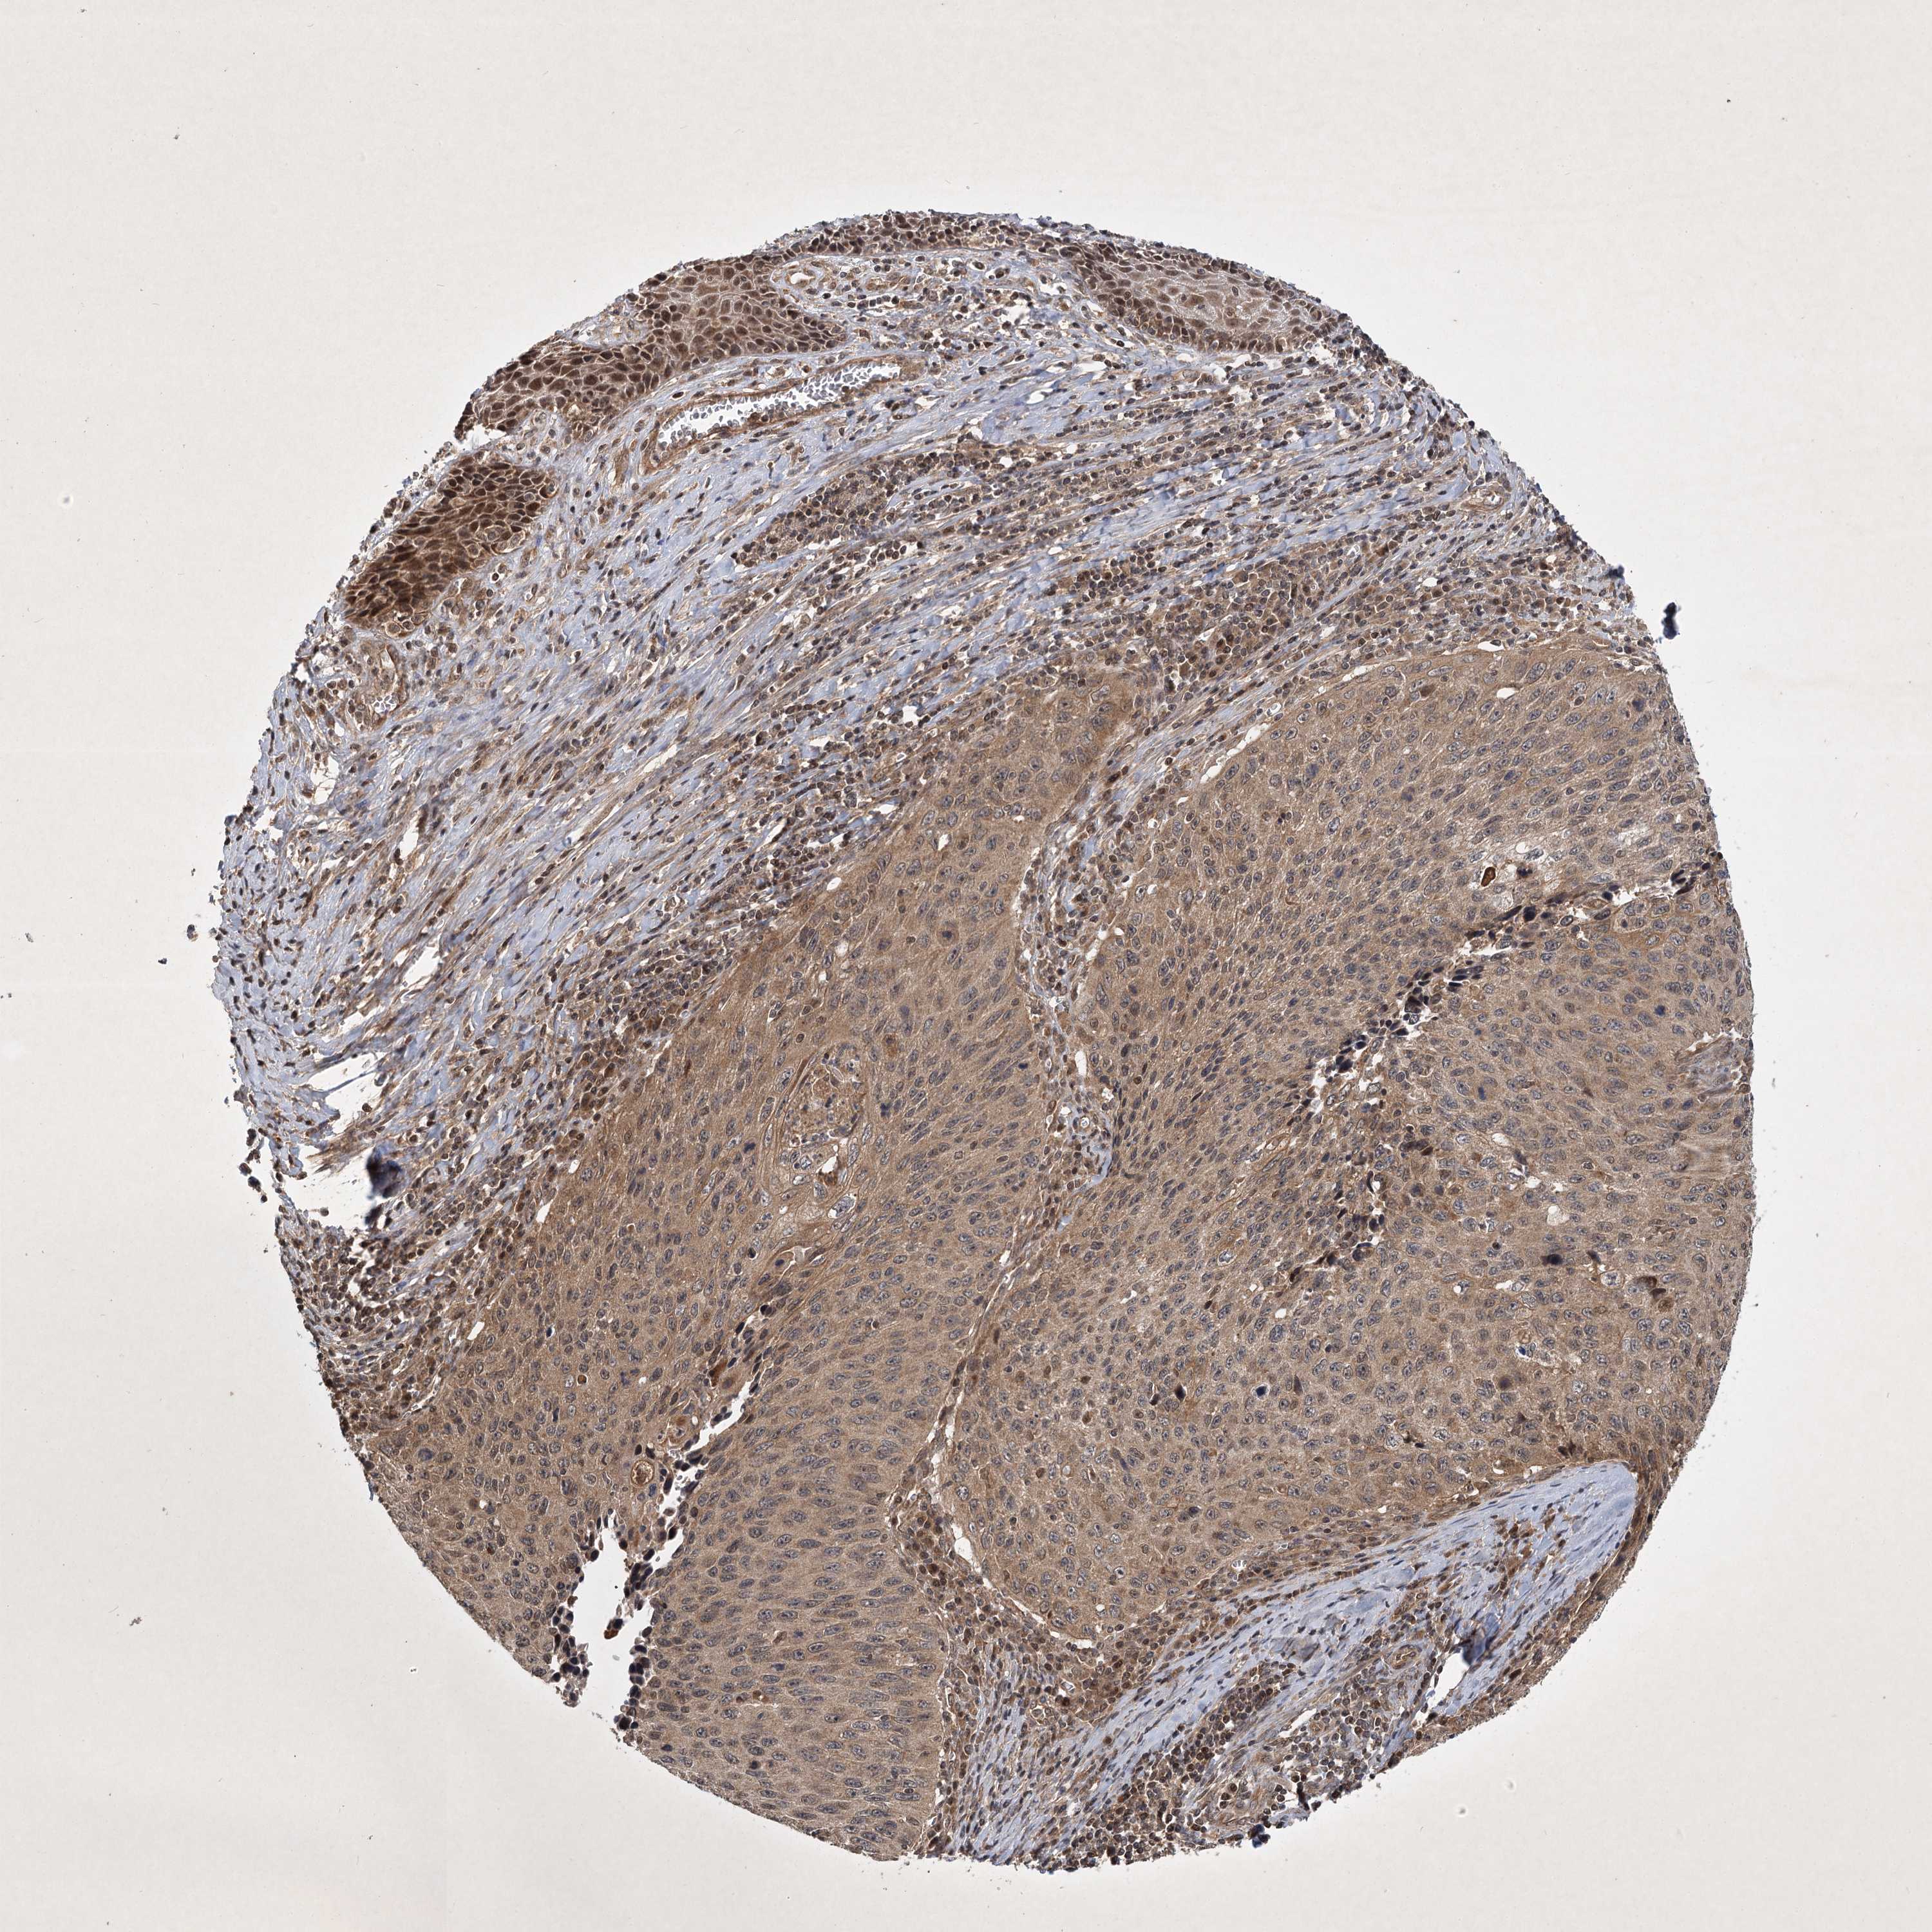

CERVICAL CANCER - Protein expressioni

A mouse-over function shows sample information and annotation data. Click on an image to view it in a full screen mode. Samples can be filtered based on level of antibody staining by selecting one or several of the following categories: high, medium, low and not detected. The assay and annotation is described here.

Note that samples used for immunohistochemistry by the Human Protein Atlas do not correspond to samples in the TCGA dataset.

Antibody stainingi

Antibody staining in the annotated cell types in the current human tissue is reported as not detected, low, medium, or high, based on conventional immunohistochemistry profiling in selected tissues. This score is based on the combination of the staining intensity and fraction of stained cells.

Each image is clickable and will lead to virtual microscopy that enables deeper exploration of all samples and also displays staining intensity scores, fraction scores and subcellular localization as well as patient and tissue information for each sample.

Antibody CAB033861

Staining

High

Medium

Low

Not detected

Intensity

Strong

Moderate

Weak

Negative

Quantity

>75%

75%-25%

<25%

None

Location

Nuclear

Cytoplasmic/membranous

Cytoplasmic/membranous,nuclear

Squamous cell carcinoma, NOS

Adenocarcinoma, NOS